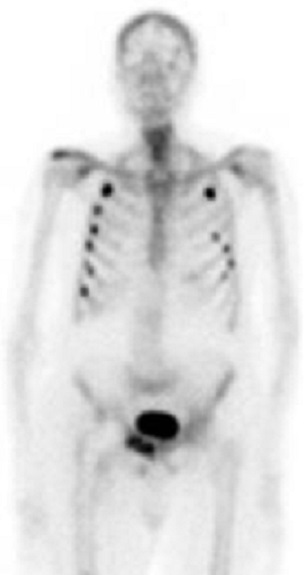

Dans cas de difficile de evaluer des cas

fracture discrete la

scintigraphie osseuse au Tc-99m peut en detecte et se

determiner . Image radiologique de scintilographie

de fracture discrete des côtes du flanc droit et

gauche du thorax |